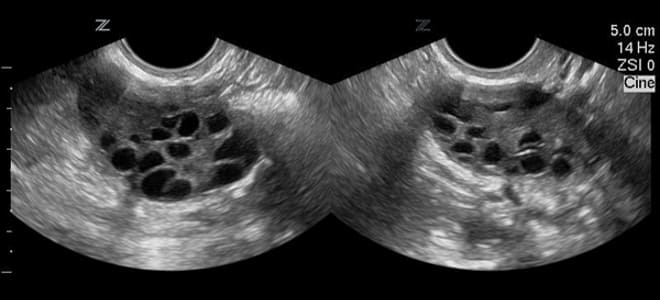

Поликистоз

При наличии синдрома поликистозных яичников (СПКЯ) ультразвуковое исследование позволяет выявить как минимум 10 фолликулов, которые располагаются в виде ожерелья из жемчуга.

В случае развития данной патологии парные половые железы увеличиваются в объеме. УЗИ у пациенток с поликистозом показывает наличие не менее 10 патологических образований в придатках, каждое из которых достигает размера 1 см.